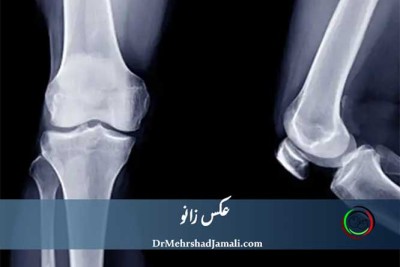

عکس زانو: همه چیز درباره انواع رادیوگرافی، تشخیص درد و آسیب‌های زانو

آیا زانو درد دارید و نمی‌دانید چه آزمایشی مناسب است؟ عکس زانو (X-Ray Knee) یکی از ساده‌ترین و سریع‌ت